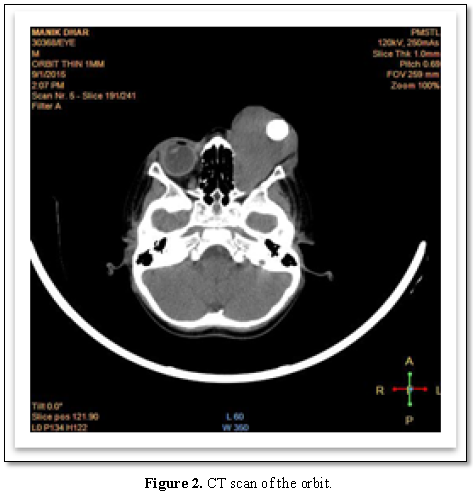

contrast enhanced CT scan on the orbit shows soft tissue mass lesion

approximately 5.6 cm × 4.7 cm × 4 cm seen completely filling the intraconal and

extraconal compartments of the left orbit. CT scan of the brain showed no signs